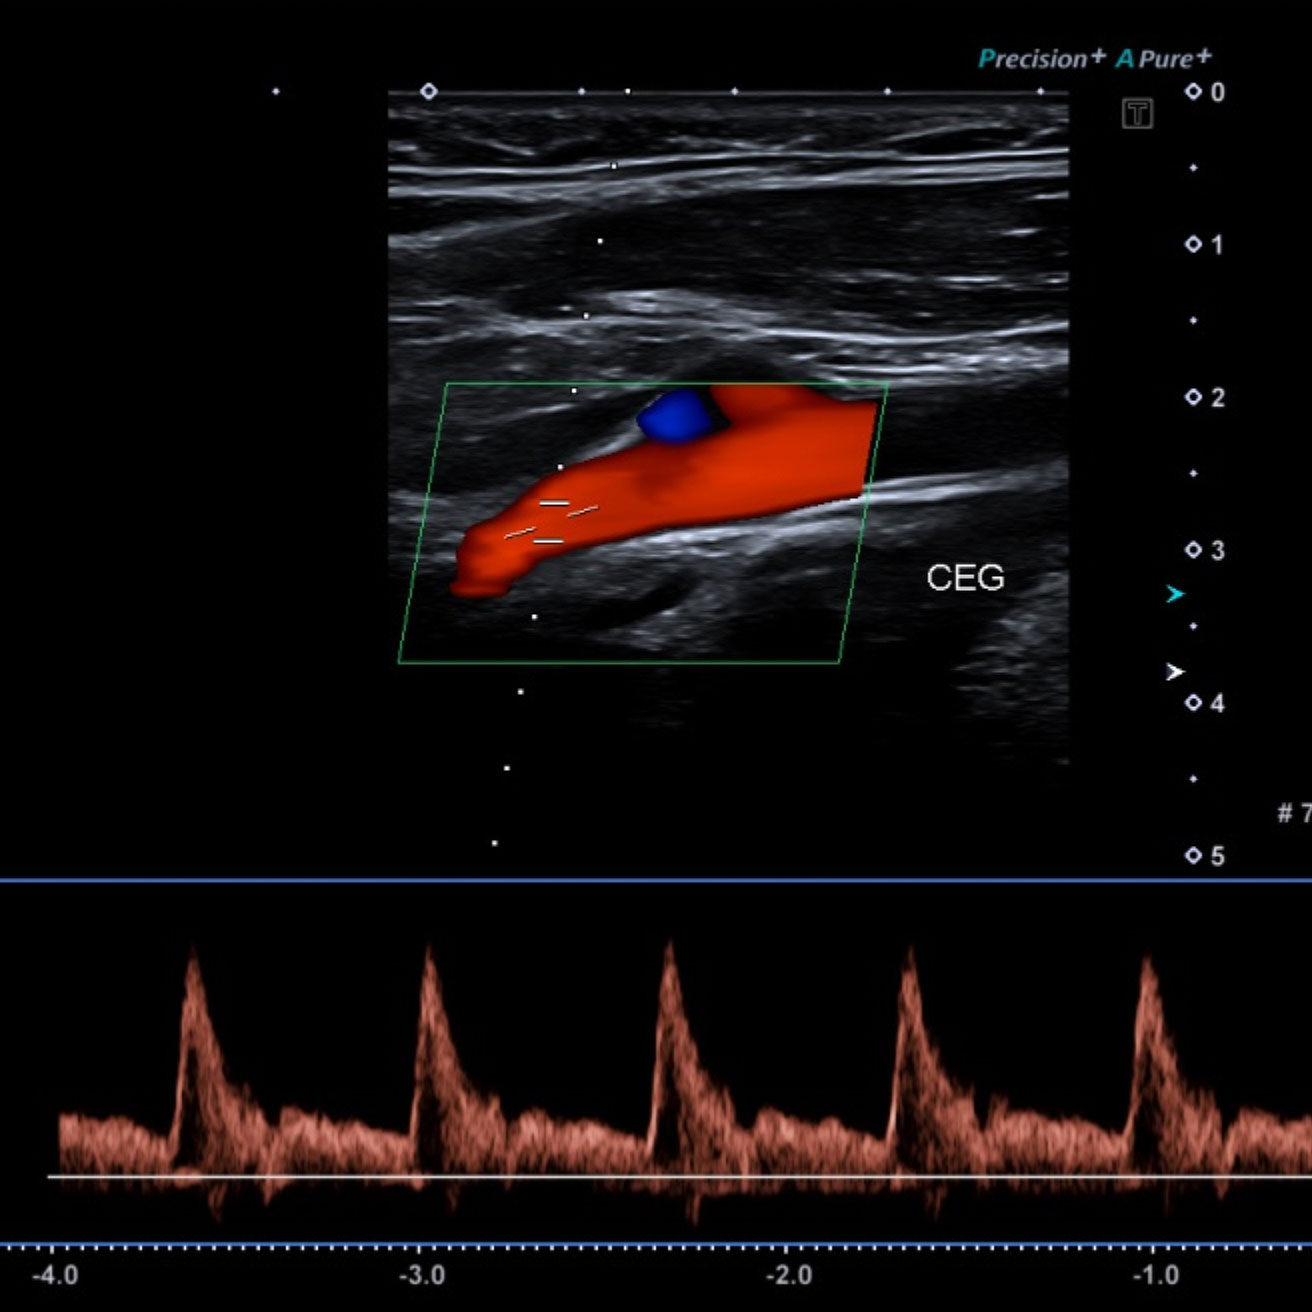

Doppler veineux et artériel images d'examen